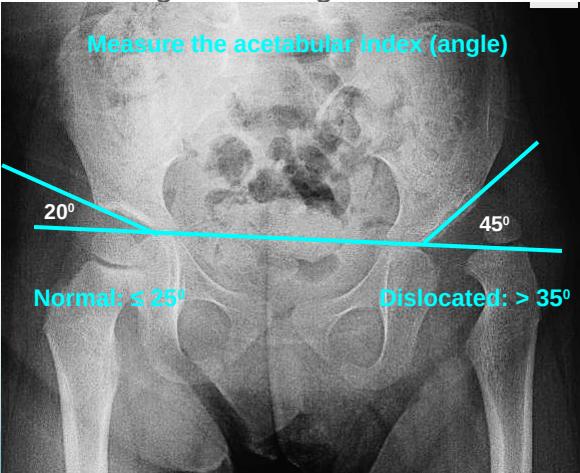

3. Acetabular Index (Acetabular Angle)

- Measurement: Angle from acetabular edge to base at horizontal line

- Normal: ≤ 25°

- Dislocated: > 35°